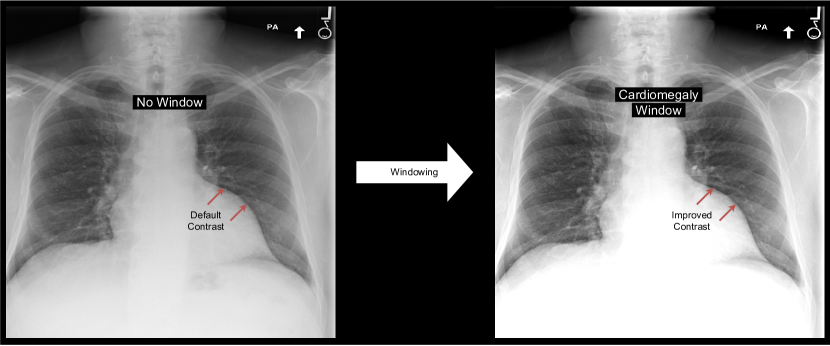

Figure 1: Applying a windowing operation enhances the contrast of particular structures of an image. For example, the depicted windowing operation improved cardiomegaly classification performance on the MIMIC data set.

Under optimal conditions, the human eye can differentiate between 700 and 900 shades of gray, or 9- to 10-bit depth (Kimpe and Tuytschaever, 2007). Hence, radiologists cannot differentiate all 12-bit gray values when inspecting a chest X-ray. To better identify subtle contrasts, they apply a windowing operation to the image: they increase the contrast by limiting the range of gray tones (see Figure 1). These windowing operations can be specified by their center (level) and width.